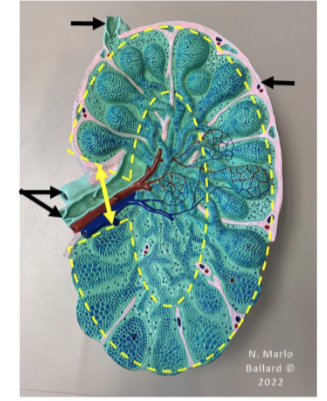

Superarenal vein

Drains blood from the adrenal (suprarenal) glands

Right suprarenal vein → inferior vena cava

Left suprarenal vein → left renal vein

Important asymmetry between right and left sides